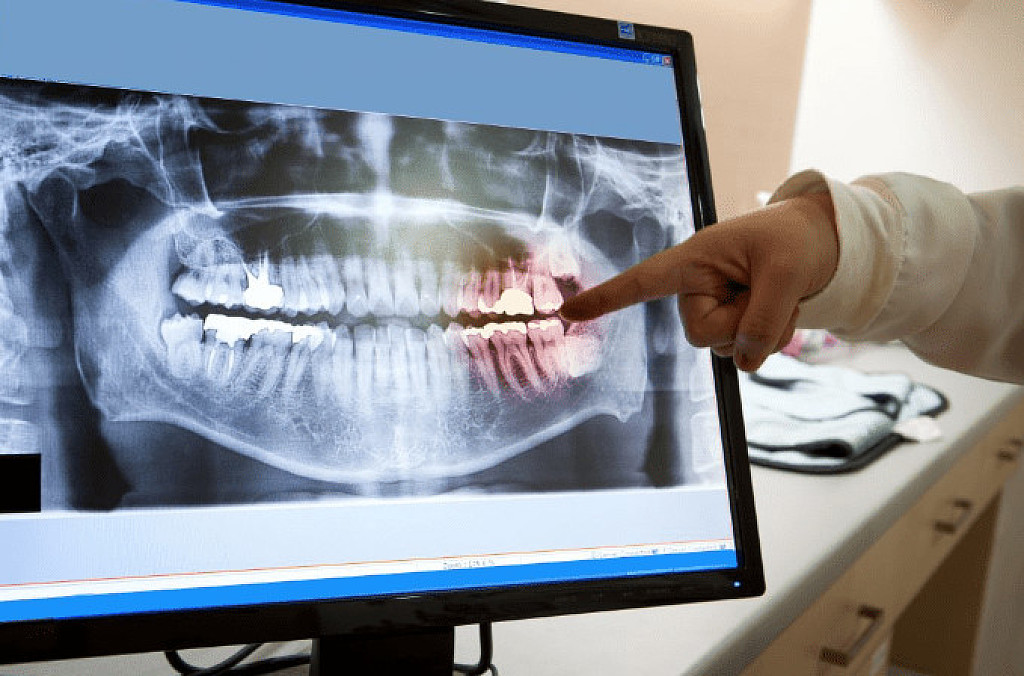

Why Do Dentists Insist on X-Rays?

A simple oral exam only allows a dentist to see the visible surfaces of the teeth and the insides of the oral cavity. With the help of an X-ray, dentists can visualize the structures present within the tooth cavity as well as the supporting bone. This allows them to detect and treat dental issues that may otherwise remain undiagnosed and lead to more problems.

Panoramic X-Ray:  This is a type of sizeable dental X-ray that requires a separate machine. The X-ray provides a detailed image of all the teeth in both lower and upper arches, along with the bone and supporting structures. They are usually used for extensive dental work like multiple extractions, braces, dental implants, etc.